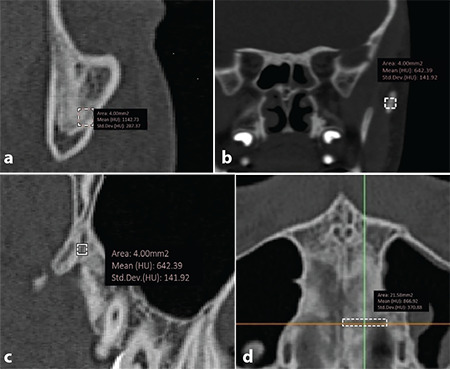

Methods: A Digital Imaging and Communication in Medicine dataset of 20 patients (mean age: 15.55 years) prior (T0) and after (T1: 3.5±0.5 months) to RME were retrieved from the archive and analyzed. Bone density values of midpalatal suture (MPS), zygomaticomaxillary suture (ZMS), zygomaticotemporal suture (ZTS), pterygopalatine suture (PPS), and transverse palatine suture (TPS) were measured. The cervical vertebral maturational stages (CVS) were examined. The linear distances between the most lateral points of the piriform apertures were measured as the anterior reference, and the medial margins of the greater palatine foramina on the axial slice were chosen as the posterior reference. The difference at T1-T0 was calculated as the skeletal response to RME at anterior and posterior skeletal references. Spearman's rho rank and Kruskal-Wallis tests were used.

Results: Mean density values of ZMS, PPS, ZTS, TPS, MPS-Anterior, and MPS-Posterior were 922.81, 807.44, 753.83, 640.77, 661.13, and 604.59 HU, respectively. Mean linear changes in anterior and posterior skeletal expansion were 2.93±1.78 and 1.93±2.52 mm. There was no significant relationship between maturation indicators and skeletal response. Significant relationships were found between CVS and MPS density and CVS and circummaxillary suture average density (p≤0.05).